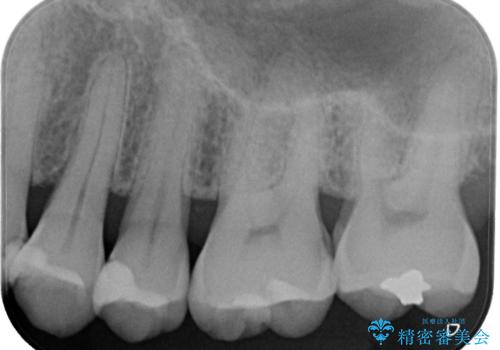

レントゲンで虫歯を発見 セラミックインレー

- 海外渡航前に、口腔内の悪いところを治しておきたいという患者様です。特に症状はない部位でしたが、レントゲンにて綿密にチェックしたところ、外側からは分かりにくい部分に虫歯が広がっているのを発見しました。隣の歯の金属も劣化しており、辺縁から感染を起こす恐れがあることが分かりました。一度の麻酔で一緒に治療が可能な範囲でしたので、2歯一緒にセラミック修復をいたしました。術後の経過も良好とのお電話を、わざわざ患者様からいただきました。